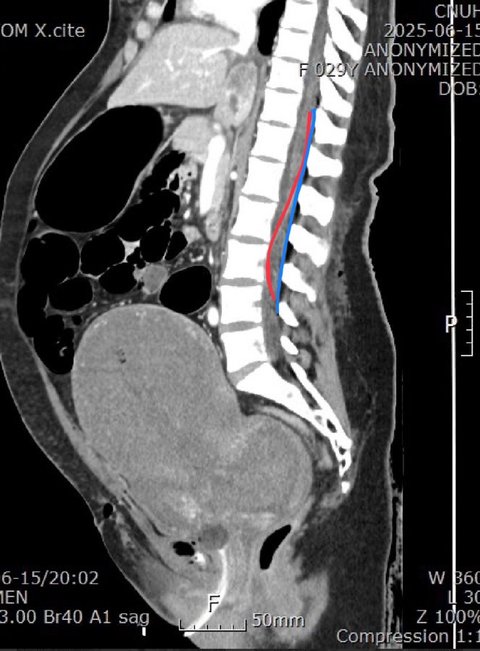

* (+추가) 사진을 보시면 경막외마취를 할 경우 파랑색 선 대로 카테터가 들어가야 하지만, 빨간색 처럼 카테터가 들어가 척추 마취가 된 것입니다. 이 사진은 언니가 이송 된 대학 병원 교수님께서 설명해 주신 부분입니다.

* 참고로 척추 마취에는 경막외마취에 비해 약물 용량이 1/10 수준으로 적어야 하며, 뇌로 약물이 흘러 들어가지 않도록 반드시 상반신을 세운 상태에서 진행하거나, 기관삽관을 병행해야 한다고 합니다.

하지만 언니의 경우 경막외마취를 하고자 했기에 이러한 사전조치 없이 척추마취가되어 호흡 불가 및 심정지에 이른 것이 아닌지 의문이 듭니다.